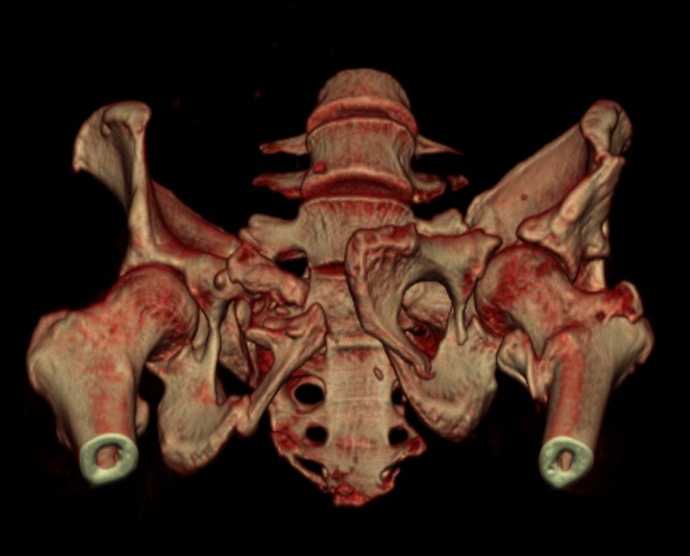

Больная 43 года (промышленный альпинист), 28.07.08 в результате падения с 5 этажа получила политравму: Перелом свода и основания черепа. Вертикально-нестабильное повреждение таза, осложнённое разрывом мочевого пузыря. Чрезвертельный перелом левого бедра. Перелом правой таранной кости, переломовывих правой кубовидной кости. Тупая травма живота, разрыв печени, ушиб почек. Забрюшинная гематома. В день травмы - лапаротомия, ушивание ран печени. Разрыв мочевого пузыря не диагностирован. Течение болезни осложнилось развитием мочевого затёка и обширной пред- и забрюшинной флегмоны, сформировался свищ мочевого пузыря. 19.8.2008 вскрытие, дренировние флегмоны, ревизия мочевого пузыря, обтурация мочевого свища (свищ закрылся в октябре), 1.10.2008 некрэктомия, пластика по Шеде-Лидскому правой кубовидной кости. По результатам КТ диагностирован рак правой почки (диагностическая находка), 8.10.2008 нефрэктомия справа. Переломы велись консервативно. Имеется вертикальное смещение левой половины таза с выраженным отведением крыла (клинически подвижности нет), несросшийся низкий двухколонный перелом левой вертлужной впадины с потерей конгруэнтности, укорочение около5 см, застарелый разрыв лонного сочленения, неправильно сросшиеся переломы обеих ветвей правой лонной кости с укорочением, патологическая подвижность лоно-седалищного фрагмента слева. Правая нижняя конечность неопорна, несмотря на то, что лежа прямую ногу поднимает, ходит на левой ноге (ортопедическая обувь) с костылями, справа тазобедренный ортез. Седалищные нервы работают.Урологи отпустили больную на 6 мес.

Мучаемся мыслями - как все это заставить ходить.Возможно ли первичное протезирование если просто синтезировать лонное сочленение с цементом и ванкомицином? Если делать большую реконструкцию, то с чего начать? Изрубить крыло и заполнить дефекты? Перерубить боковую массу и попытаться развернуть крыло обратно? Ждать год после закрытия свищей?

с большей вероятностью пациентка придет к эндопротезированию тазобедренного сустава, поэтому необходимо создать надежную "опору" сзади и подготовить бедро к имплантации любой классической ножки.ИМО бедренной кости GN, АНФ на таз,по необходимости остеотомия крестца, восстановление конфигурации задних отделов и устранение вертикального смещения половины таза. дождаться сращения крестца и бедренной кости. второй этап эндопротезирование: ножка цвай-мюллер или спаторно,ацетабулярно онкологическое антипротрузионное кольцо левое либо ацетабулярный компонент по индивидуальным параметрам для протезирования после резекции лонной седалищной костей и вертлужной впадины при онкопатологии. в кольцо пару трения металл\металл с цементной чашкой IMPLANTCAST, т.к. пациентка молодая.лонные кости можно оставить в покое, какой никакой рубец есть. с уважением Сергей.